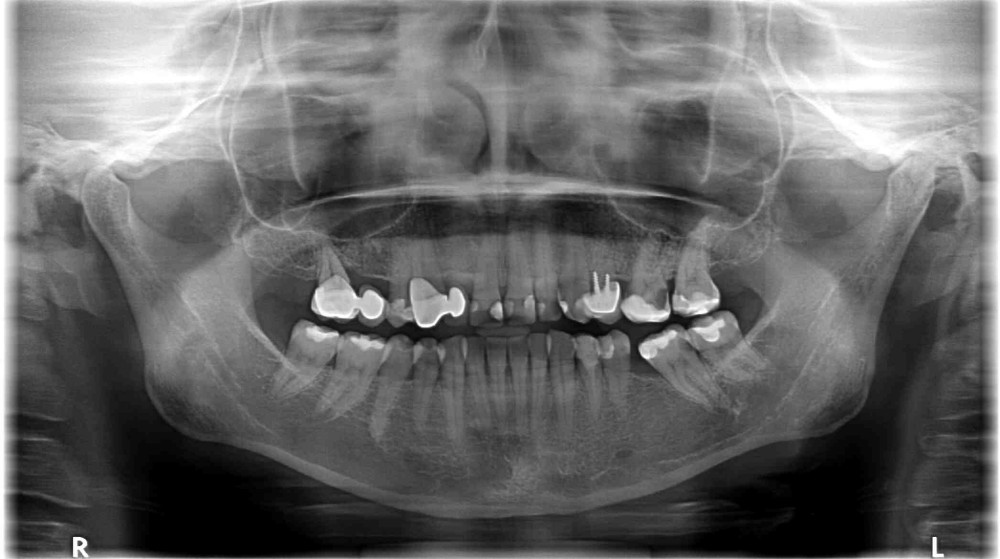

Dokumentacja RTG

- OPG przed zabiegiem wykonane przez lekarza prowadzącego

- RVG

- CBCT przed i po zabiegu